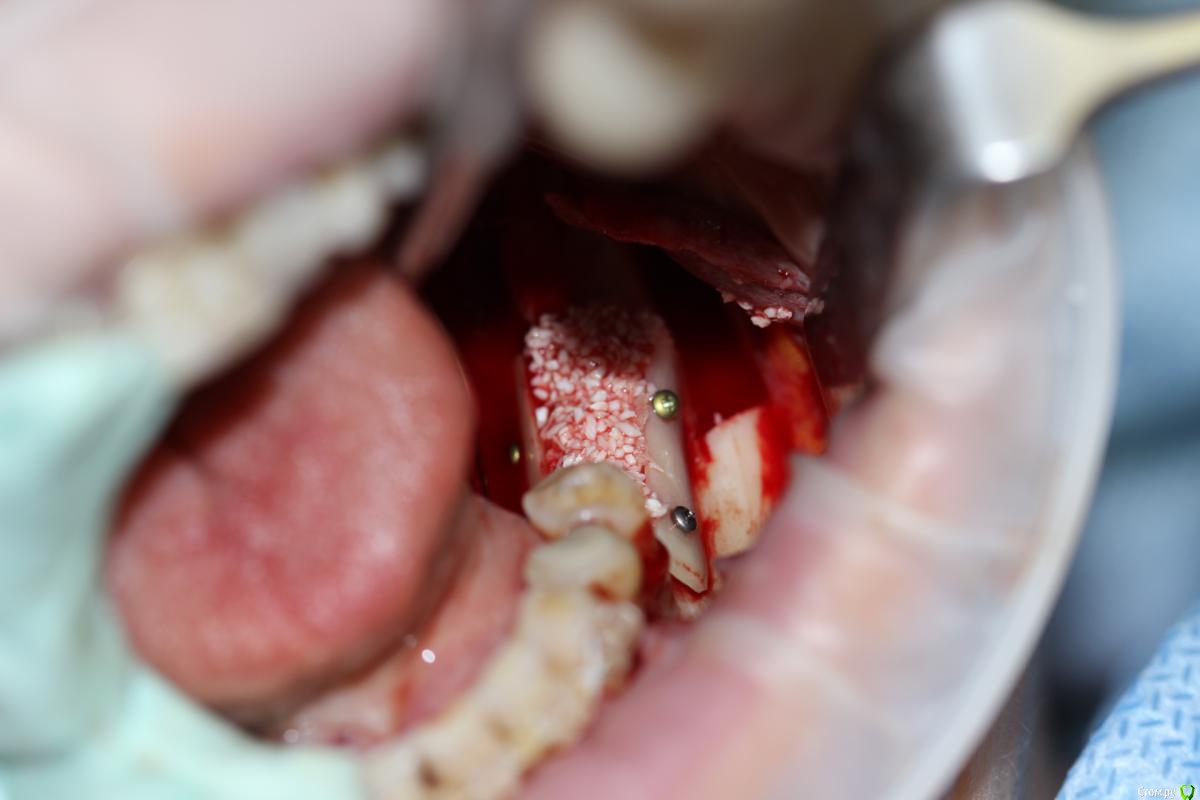

АнтонТЛТ Опубликовано 22 декабря, 2014 Поделиться Опубликовано 22 декабря, 2014 Название темы не соответствует выложенному кейсу. Тут не блоки, а ламинаты. И в классике нет графта, чистый ауто Ссылка на комментарий

Sahan Опубликовано 22 декабря, 2014 Поделиться Опубликовано 22 декабря, 2014 В четвертом сегменте во время имплантации дополнительно костную пластику проводили? Ссылка на комментарий

Dantist55 Опубликовано 22 декабря, 2014 Автор Поделиться Опубликовано 22 декабря, 2014 В четвертом сегменте во время имплантации дополнительно костную пластику проводили?Да, имплантация с НКР. Ссылка на комментарий